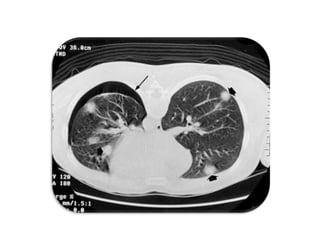

3. TDM thoracique

pleurale

• La TDM thoracique n’est pas nécessaire au

diagnostic mais indiquée si la

symptomatologie évocatrice contraste avec

une RX thorax normale

• Par contre sa pratique est courante pour le

diagnostic étiologique et dans la discussion

d’un geste thérapeutique radical

• Elle permet aussi d’apprécier le risque de

récidive en précisant le nombre le volume et

la topographie des bulles

Résultats :

• Le PNO apparaît sous forme d’une plage noire

qui refoule le poumon comparé à un croissant

gazeux